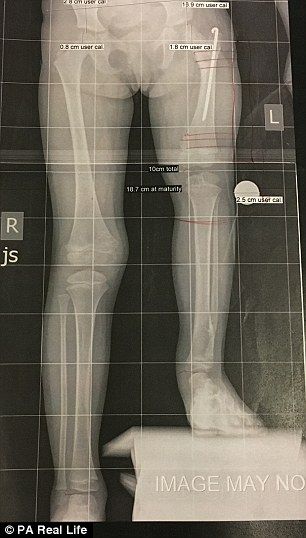

Contactó con el doctor Shawn, experto en discapacidades de este tipo, y decidieron someter a la menor a una complicada operación para alargar su pierna. Tras seis largas horas en quirófano, los médicos pudieron dar la noticia: habían conseguido reconstruir la cadera, el tobillo y la rodilla.

Así, Elsie consiguió andar con 21 meses, pero lo más duro vendría aún. Después de la cirugía, su madre se comprometió a activar manualmente los tornillos de la prótesis que le colocaron para separar el fémur y la tibia tres veces al día. Por tanto, fracturaron la pierna izquierda de la pequeña Elsie 300 veces a lo largo de cuatro meses, y consiguieron lo que pretendían, que la pierna corta se alargase 10 centímetros.